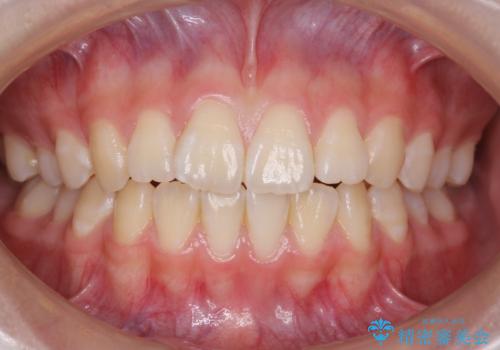

![[ インビザライン矯正 ] マウスピース矯正で治す、前歯のガタつきの症例 治療後](https://seimitsushinbi.jp/wp/wp-content/uploads/2022/02/IMG_1698-500x350.jpg?v=1644473356)